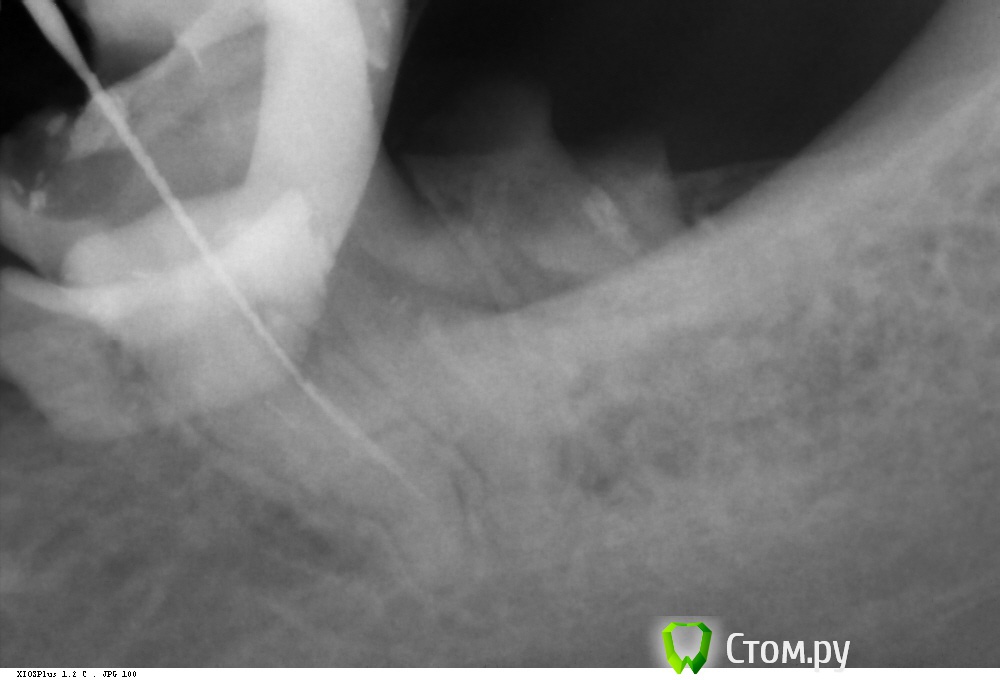

Kolchanov Опубликовано 14 июня, 2014 Автор Поделиться Опубликовано 14 июня, 2014 Ниасилил. Видел чуть-чуть, но достать не смог.http://i062.radikal.ru/1406/eb/40c8cc9253c3.jpghttp://s019.radikal.ru/i623/1406/ac/d1ad0e5bbf5e.jpghttp://s020.radikal.ru/i716/1406/98/1b06aedec191.jpg Ссылка на комментарий

Kolchanov Опубликовано 14 июня, 2014 Автор Поделиться Опубликовано 14 июня, 2014 Два по два. Больше чем здесь развернуть не удалось. Может и сходятся, во всяком случае, до начала отломка перешеек есть. Можно было бы расшить, но я не стал. Какого черта? Зуб года под штампованным мостом ходил, не беспокоил никак.Там от 8ки проблем больше.Мелкоскоп надо... С мелкоскопом добыл бы. Ссылка на комментарий

Kolchanov Опубликовано 15 июня, 2014 Автор Поделиться Опубликовано 15 июня, 2014 Где-то час я ему (отломку) уделил точно Сколько можно в него тыкать и отмывать? Тут доступ был сделан к нему 3 гейтсом. Возможно, что засади я 4ым, то смог бы его лучше разглядеть. Но зубу мог бы запросто настать пипец. Глубина до отломка 15 мм. Ссылка на комментарий